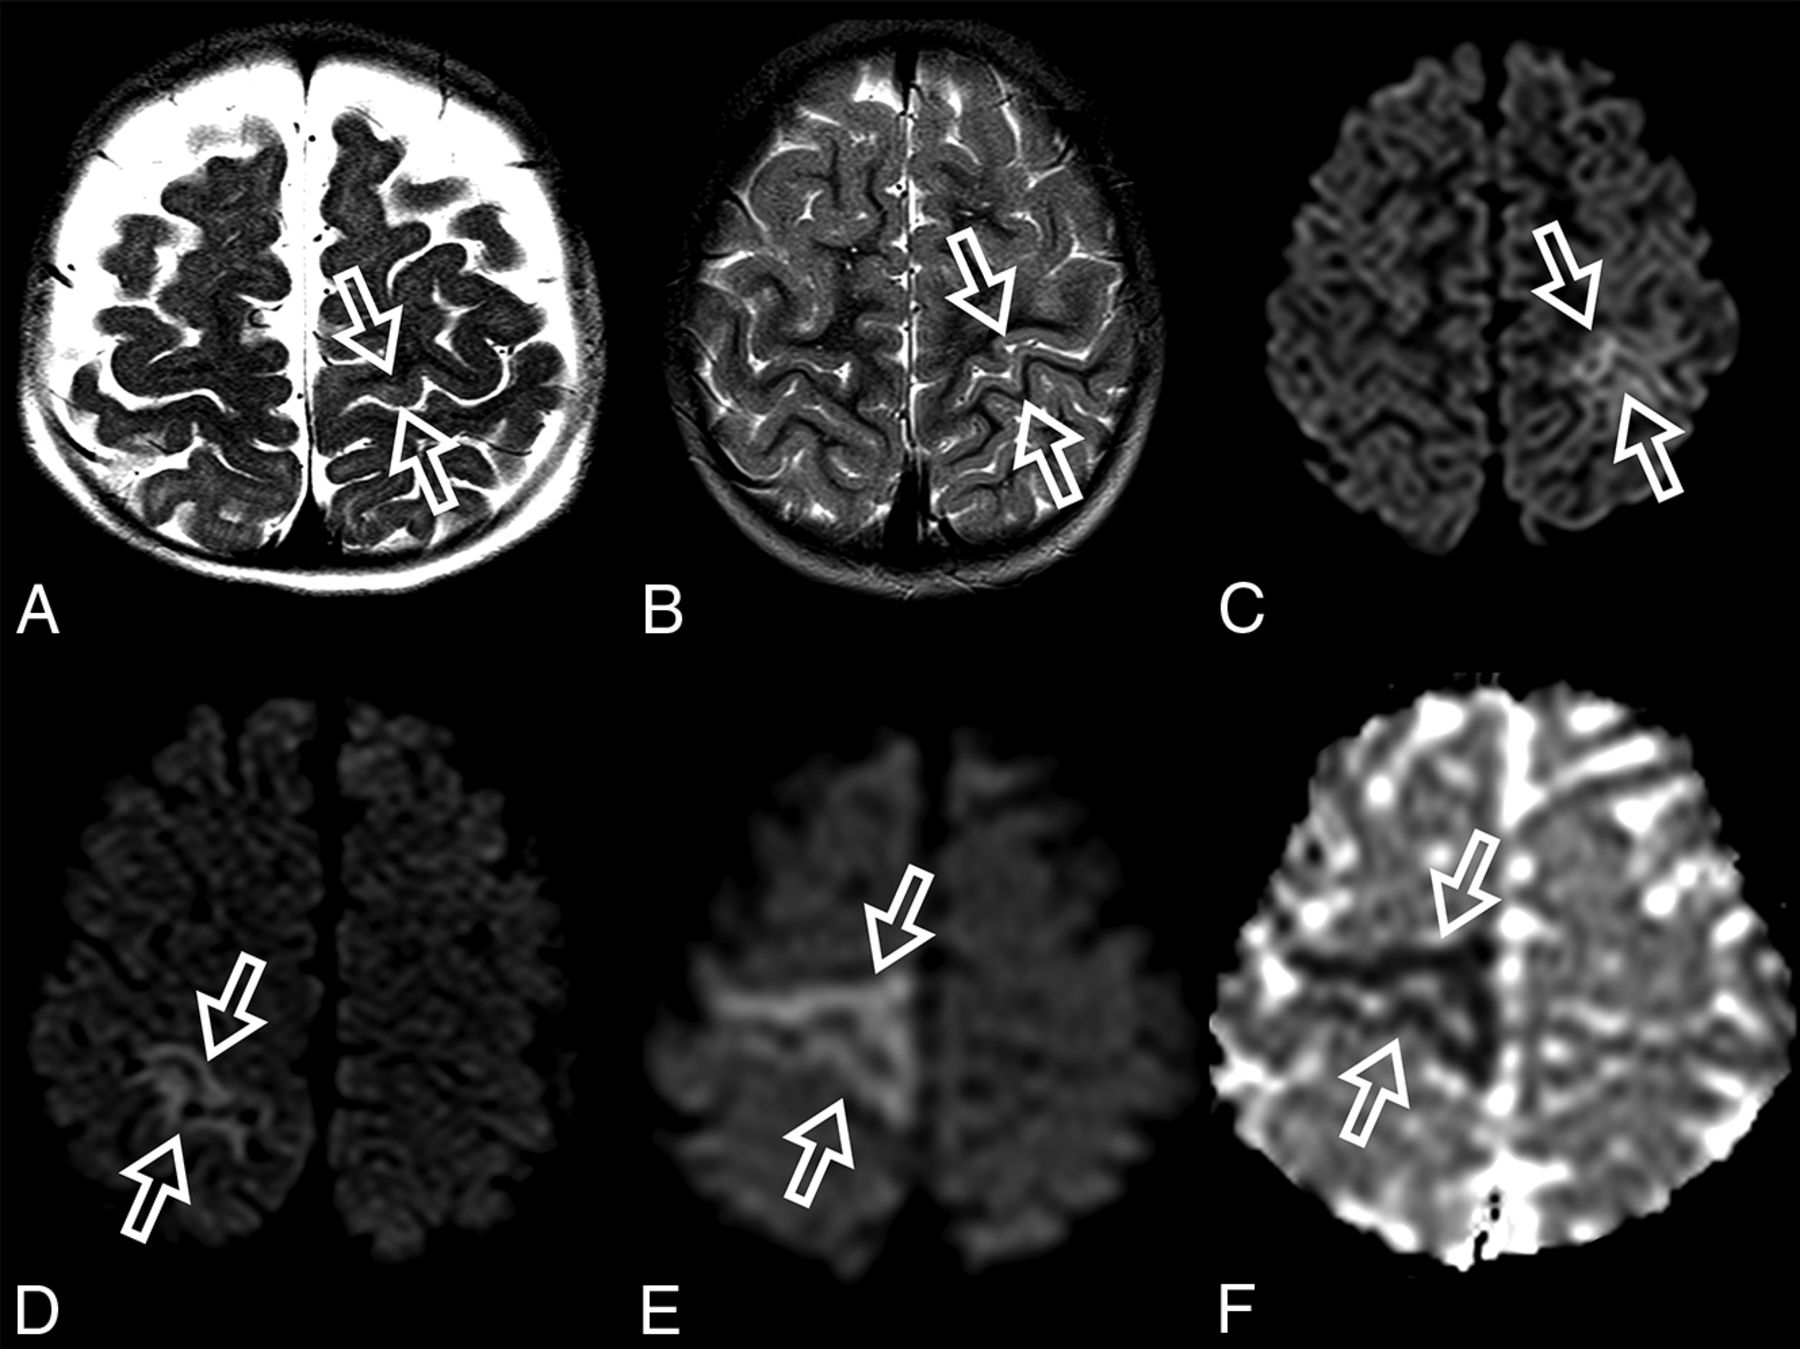

Perirolandic sign in 4 different patients with POLG-related disorders (A, An 8-month-old female), (B and C, A 3 year-old-male), (D, An 1-year-old male) and (E and F, A 9-month-old female). Signal changes around the central sulcus were variable with varying degrees of conspicuity. A, T2WI. Signal changes are subtle and focal, evident only in the left precentral gyrus (open arrows). B, T2WI. Signal changes are subtle and focal, evident in the left pre- and postcentral gyrus (open arrows), but more conspicuous in the DWI (open arrows, C). D, DWI. Linear signal changes involving mainly the cortex surrounding the right central sulcus (open arrows). E and F, DWI and ADC map, respectively. Marked signal changes in both right pre- and postcentral gyri.

The MR imaging appearance of the perirolandic sign was varied. Signal changes involved both the pre- and postcentral gyri, more commonly in the precentral gyri. The conspicuity of the perirolandic sign was also variable (Fig 1). In the more notable cases, signal changes were ribbon-like following the course of the gyri, which were readily detectable as T2 hyperintensities and restricted diffusion. DWI was the most sensitive MR imaging sequence to detect signal changes and, therefore, should always be included in the protocol and carefully evaluated when a case of POLG-RD is suspected.